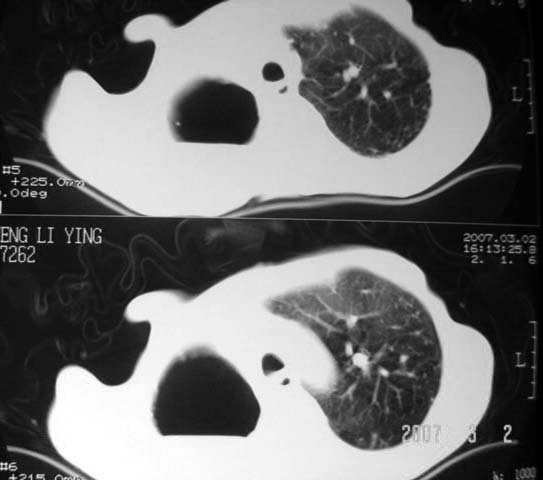

以下是引用dyqct在2007-3-2 22:04:00的发言:[br]考虑:1、右侧毁损肺伴支气管胸膜瘘(多条支气管与胸腔相通、液气胸);[br] 2、左肺浸润型肺结核。[br][br][br][br]